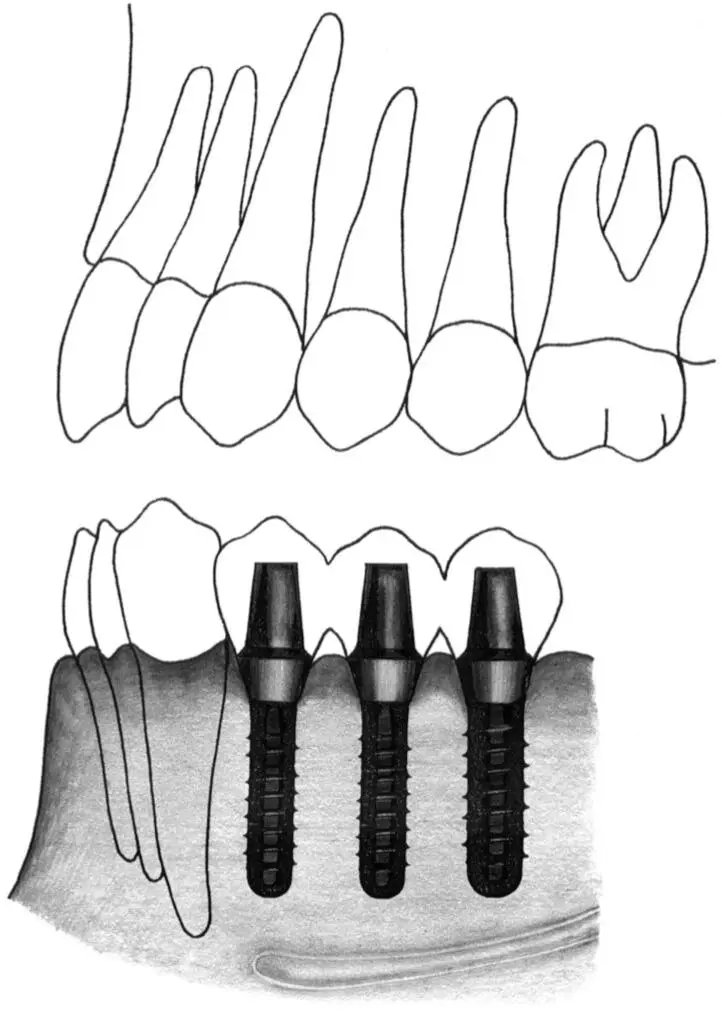

Fig 2-3 Wide body implant.

Fig 2-3a Shorter and wider implants are indicated in the posterior maxilla to avoid the maxillary sinus. A standard implant is indicated in the second premolar site, and a wide body implant is indicated in the first molar site.

Fig 2-3b Shorter and wider implants are also indicated in the posterior mandible to avoid the mandibular canal. Two wide body implants can be placed in the first and second molar sites. These implants are restored and, in cases of short 6-mm implants, routinely splinted.